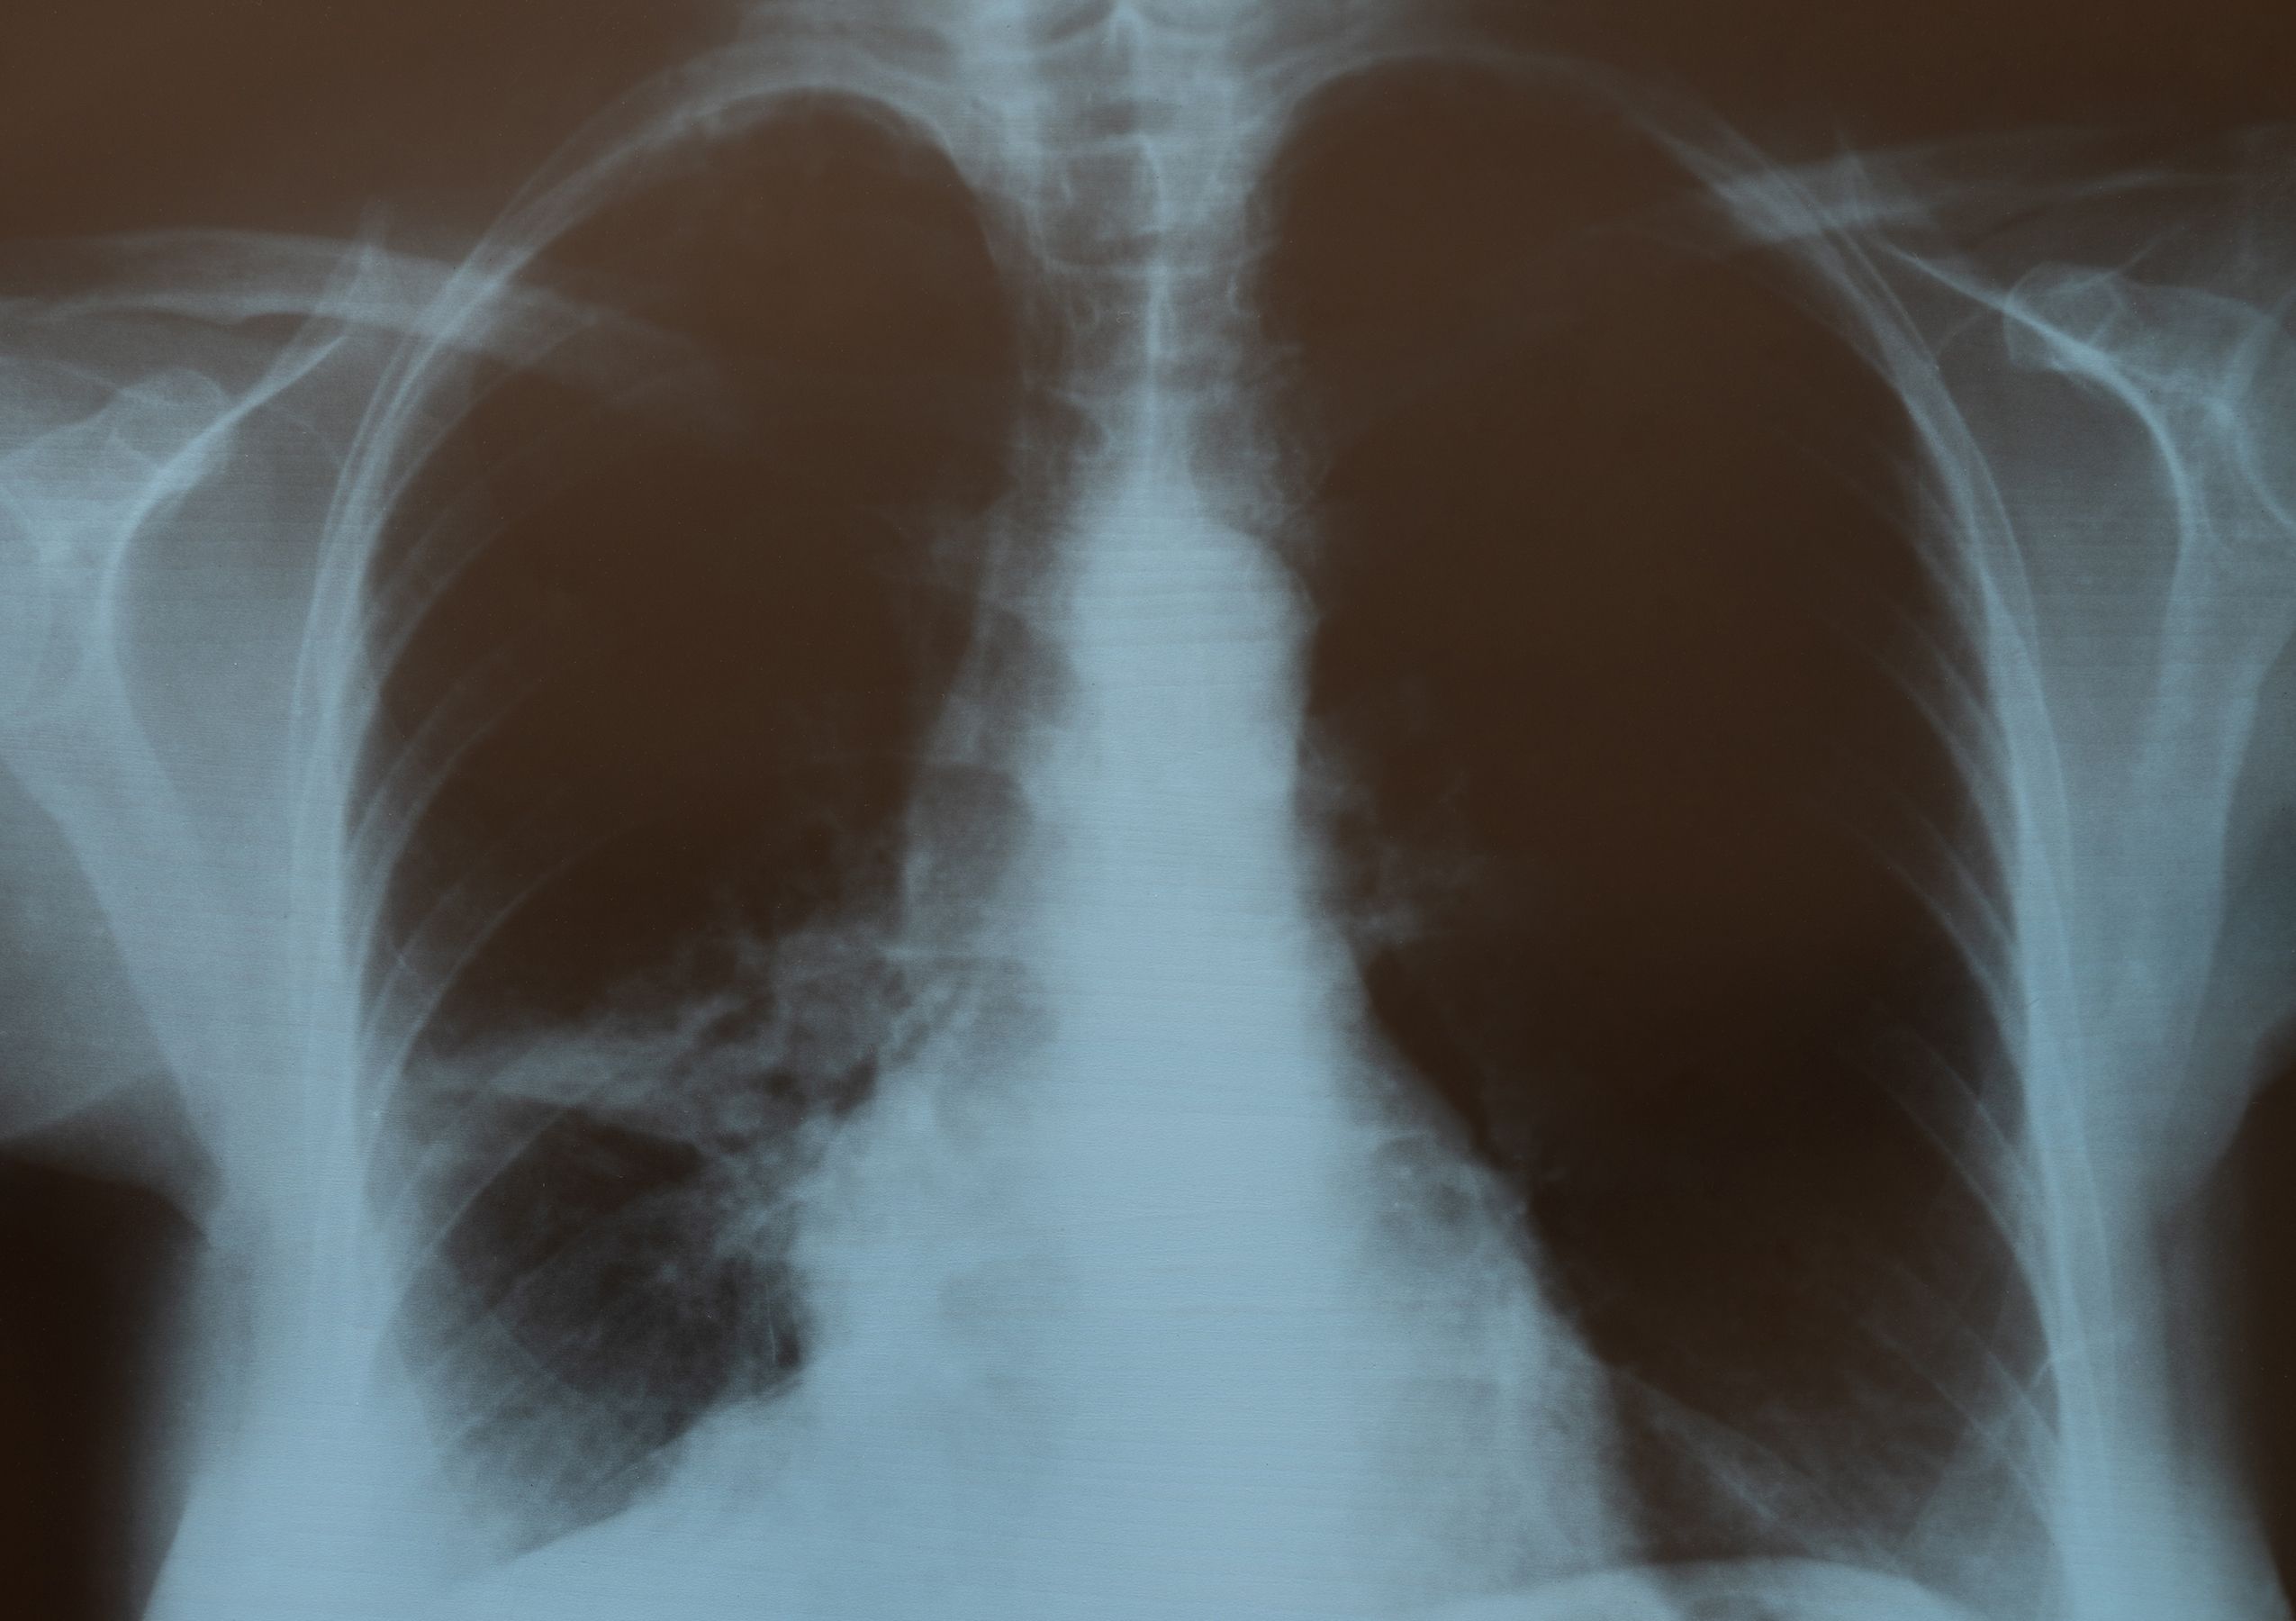

Las biopelículas de esta bacteria crecen en la superficie de los tubos endotraqueales utilizados por pacientes en estado crítico quienes, por lo tanto, requieren ventiladores mecánicos para respirar.

Neumonía asociada al ventilador

Esto causa neumonía asociada al ventilador (NAV), una afección que afecta hasta uno de cada cuatro (9-27%) pacientes que requieren intubación, y la incidencia supera el 50% en el caso de los pacientes intubados por covid-19 grave.

La NAV puede prolongar la estancia en la unidad de cuidados intensivos hasta un periodo de trece días, y tiene una tasa de mortalidad que alcanza a uno de cada ocho pacientes (9-13%).